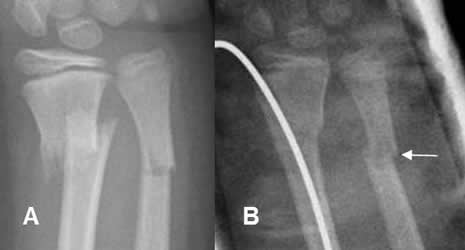

Fig 79. Inflamación.

A: Rx AP. Fractura cabalgada del radio distal y en leño verde del cúbito.

B: Rx AP. Reducción y fijación con clavo de la fractura del radio. Osteoporosis localizada en el foco de fractura del cúbito, por hiperemia.